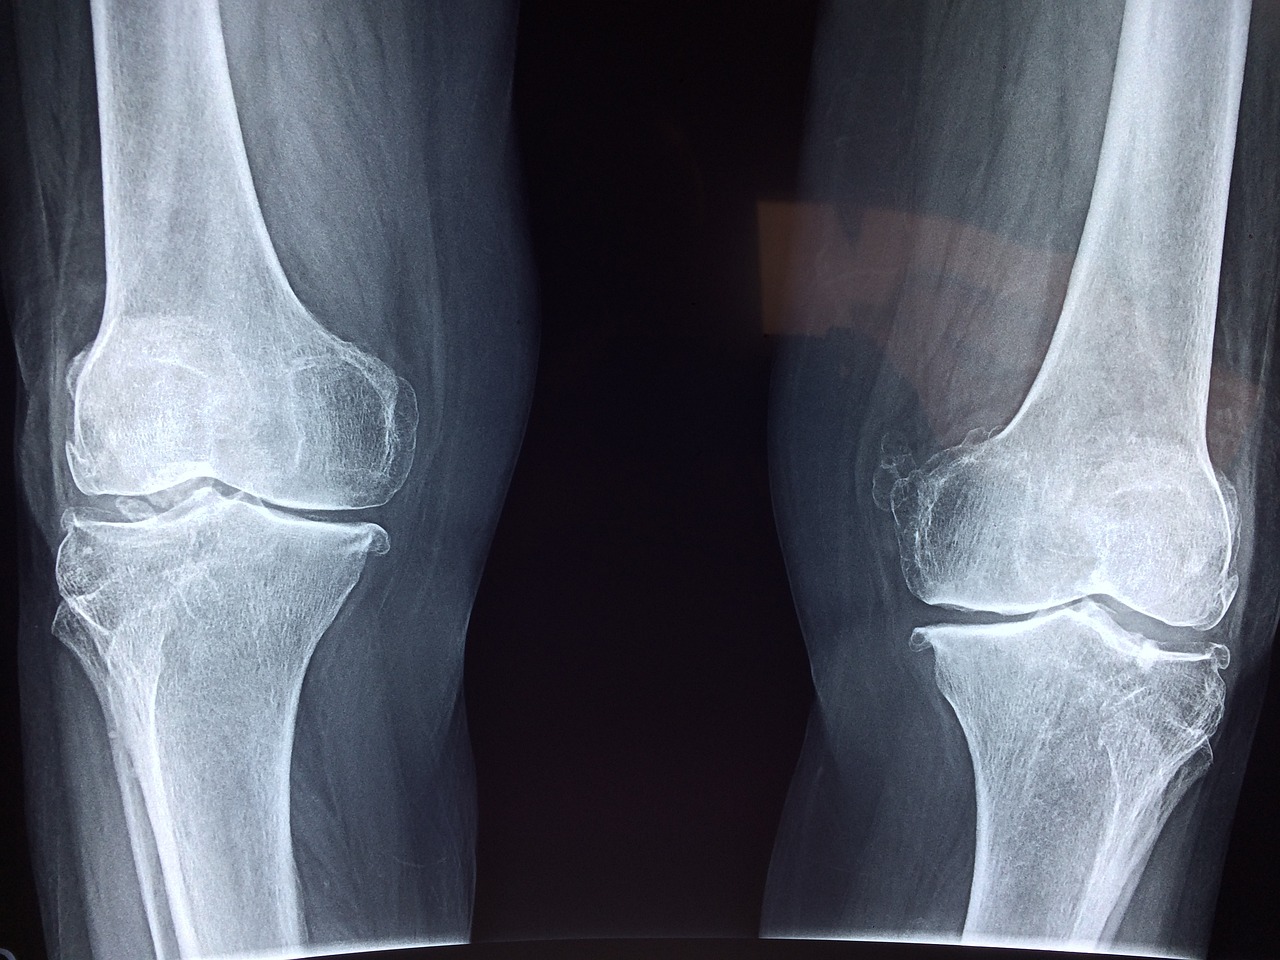

콘드로이친은 우리 몸의 연골 조직에서 발견되는 성분으로, 관절을 부드럽게 유지하고 충격을 흡수하는 데 중요한 역할을 합니다. 나이가 들면서 체내 콘드로이친의 양이 감소하게 되는데, 이는 관절이 약해지고 퇴행성 관절염과 같은 질환이 발생하는 원인이 됩니다. 따라서 이를 보충해주는 콘드로이친 영양제를 섭취하면 관절 건강을 유지하는 데 도움이 됩니다.

콘드로이친은 연골 보호 및 관절 기능 개선에 긍정적인 영향을 미칩니다. 첫째, 연골의 손상을 예방하고 회복을 촉진하여 관절염 진행을 늦출 수 있습니다. 둘째, 관절 내 윤활 작용을 도와 뻣뻣한 움직임을 부드럽게 만들어 줍니다. 셋째, 염증 반응을 억제하여 관절 통증을 완화하는 데 도움을 줍니다. 이러한 효능 덕분에 콘드로이친은 관절 건강이 걱정되는 중장년층뿐만 아니라, 스포츠 활동이 잦은 젊은 층에게도 유용한 영양제입니다.